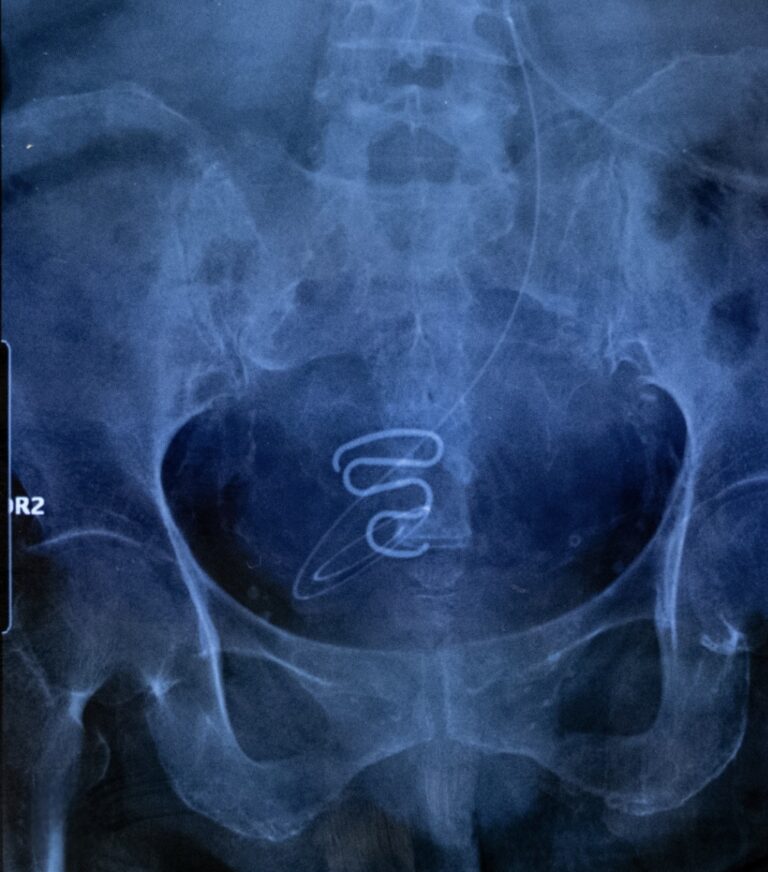

Le infilarono una spirale, un IUD, nel suo corpo senza che lei sapesse esattamente perché, cosa fosse, come andasse gestita — e soprattutto, senza il suo consenso consapevole.

“Siamo”, perché la sua voce non è un’eccezione. È il filo rosso che collega migliaia di altre donne inuit — bambine e ragazze — che tra gli anni Sessanta e Settanta (ma anche dopo) furono incluse in quello che oggi è chiamato il Spiral case, la “campagna della spirale”: un programma di controllo della fertilità orchestrato da medici e funzionari sanitari danesi, rivolto quasi esclusivamente alle donne groenlandesi, spesso minorenni, senza che i loro corpi venissero spiegati, compresi o rispettati.

Tra il 1960 e il 1975, migliaia di donne Inuit in Groenlandia furono sottoposte all’inserimento di dispositivi intrauterini — IUD — senza il loro consenso, né quello dei genitori, spesso senza che venissero informate sul loro significato o funzione. Molte ragazze avevano solo 12 anni.

Le prendevano a scuola le sottoponevano ad una visita e poi inserivano loro spirali per donne adulte che avevano partorito, creando conseguenze che decenni dopo queste donne si portano ancora addosso.

Così nacque una campagna di inserimento massiccio di dispositivi intrauterini tra le donne groenlandesi, a partire dal 1966. Formalmente una politica sanitaria. Nella pratica, una misura applicata quasi esclusivamente alle donne inuit.

Nel giro di pochi anni, la metà delle donne in età fertile in Groenlandia aveva ricevuto una spirale — spesso senza firmare alcun consenso informato. 4500 ragazzine.

Le spirali venivano inserite durante visite di routine, controlli scolastici, consulti ginecologici. A volte le ragazze non sapevano nemmeno di averle. In alcuni casi avevano 12 o 13 anni. In altri, come Inger, erano giovani donne che si fidavano del medico, dell’istituzione, della parola “per il tuo bene”.

Quella maledetta spirale, per lei e per tutte le altre, non è solo un oggetto medico: è simbolo di una violenza silenziosa, una ferita incisa nella carne della collettività inuit. È il simbolo di una logica che ha attraversato il Novecento: l’idea che alcune vite potessero essere gestite, che alcune nascite fossero meno desiderabili, che il consenso fosse un dettaglio.